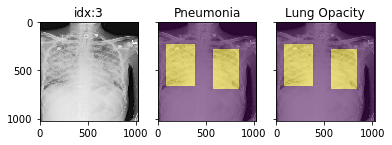

'Support Devices': {0.0: 21757, 1.0: 99747}}Pathology masks (demo notebook)

Masks are available in the following datasets:

xrv.datasets.RSNA_Pneumonia_Dataset() # for Lung Opacity

xrv.datasets.SIIM_Pneumothorax_Dataset() # for Pneumothorax

xrv.datasets.NIH_Dataset() # for Cardiomegaly, Mass, Effusion, ...Example usage:

d_rsna = xrv.datasets.RSNA_Pneumonia_Dataset(imgpath="stage_2_train_images_jpg",

views=["PA","AP"],

pathology_masks=True)

# The has_masks column will let you know if any masks exist for that sample

d_rsna.csv.has_masks.value_counts()

False 20672

True 6012

# Each sample will have a pathology_masks dictionary where the index

# of each pathology will correspond to a mask of that pathology (if it exists).

# There may be more than one mask per sample. But only one per pathology.

sample["pathology_masks"][d_rsna.pathologies.index("Lung Opacity")]it also works with data_augmentation if you pass in data_aug=data_transforms to the dataloader. The random seed is matched to align calls for the image and the mask.